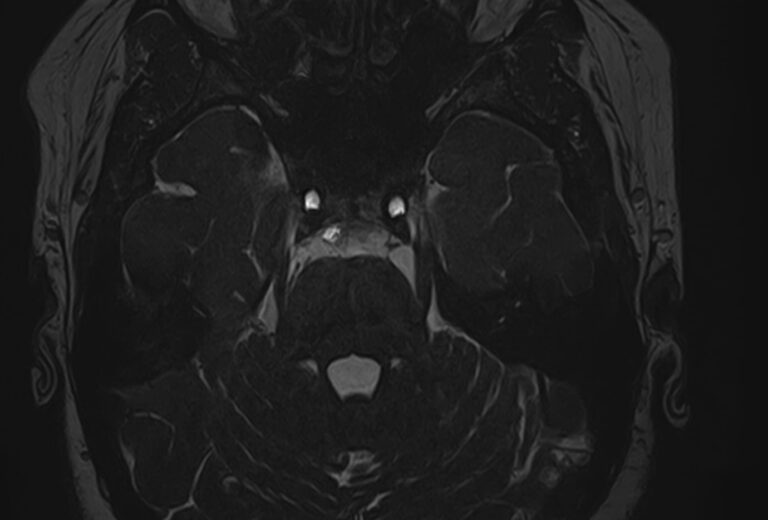

Для диагностики поражения черепно-мозговых нервов, а также оценки состояния окружающих их тканей и визуализации сосудистой сети головного мозга в клинике «Доступная медицина» проводится комплексное обследование МРТ головного мозга + Мр-ангиография головного мозга + МР-венография головного мозга + черепно-мозговые нервы. Данное обследование включает в себя несколько протоколов: стандартный – для оценки состояния всех структур головного мозга и дополнительные – для изучения очагов поражения черепных нервов и визуализации всей сосудистой системы головного мозга.

Исследования выполняются на современном высокопольном томографе экспертного класса TOSHIBA VANTAGE TITAN 1,5 Тесла, который использует разные режимы сканирования с толщиной среза от 1мм в различных плоскостях с последующей цифровой обработкой полученных данных для создания трехмерных изображений. МР-ангиография отображает состояние артериальной системы кровоснабжения головного мозга. МР-венография головного мозга позволяет детально изучить особенности венозного русла головного мозга.

Компьютерная программа обрабатывает данные, полученные при сканировании, и формирует объемные изображения как самого мозга, так и сосудистой системы в отдельности без прилегающих тканей. Методики применяются одновременно и взаимодополняют друг друга.

Данное комплексное исследование в большинстве случаев проводится с контрастным усилением, которое необходимо для улучшения визуализации черепно-мозговых нервов. Для этого внутривенно вводится препарат, содержащий гадодиамид (соли металла гадолиния) для получения изображений с высокой четкостью и контрастностью, что способствует ранней диагностике заболеваний головного мозга.